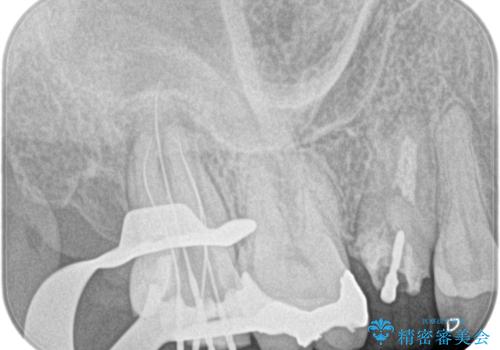

- 左上7番の奥歯に、根尖部の大きな病変を認め来院されました。レントゲンと精密検査の結果、歯の根の先に膿が溜まっている状態と診断。歯を残すことを第一に考え、精密根管治療による改善を目指す治療計画を立案しました。治療においては、細菌の侵入を徹底的に防ぎ、病変部を確実に除去するために、ラバーダムと歯科用顕微鏡を併用することを提案しました。

今回の精密根管治療では、まず治療中に唾液や細菌が入らないようラバーダムで患部を隔離しました。次に、肉眼では見えない根管内部を歯科用顕微鏡で拡大しながら確認。これにより、病変部を正確に特定し、感染源を徹底的に除去することができました。また、健康な歯質を極力残すため、必要以上に歯を削らないよう細心の注意を払って治療を進めました。治療後は、根尖部の病変がきれいになくなり、良好な経過をたどっています。これにより、大切な奥歯を残し、再感染のリスクを抑えることができました。